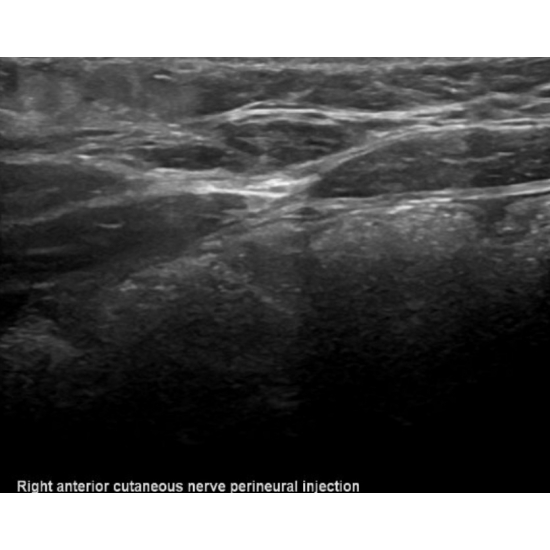

Patient returned for a diagnostic and therapeutic ultrasound guided anterior cutaneous nerve perineural corticosteroid injection. Two days post-injection, she returned to clinic with concern for post-injection steroid reaction and completed a course of oral steroids with resolution of reaction and significant improvement of symptoms. The patient had recurrence of symptom after one month and was referred to pediatric neurosurgery for planned surgical release and neurectomy procedure with pediatric plastic surgery. Photos below demonstrate the pre and post perineural injection visualization, respectively.

Case Photo #3 , Case Photo #4